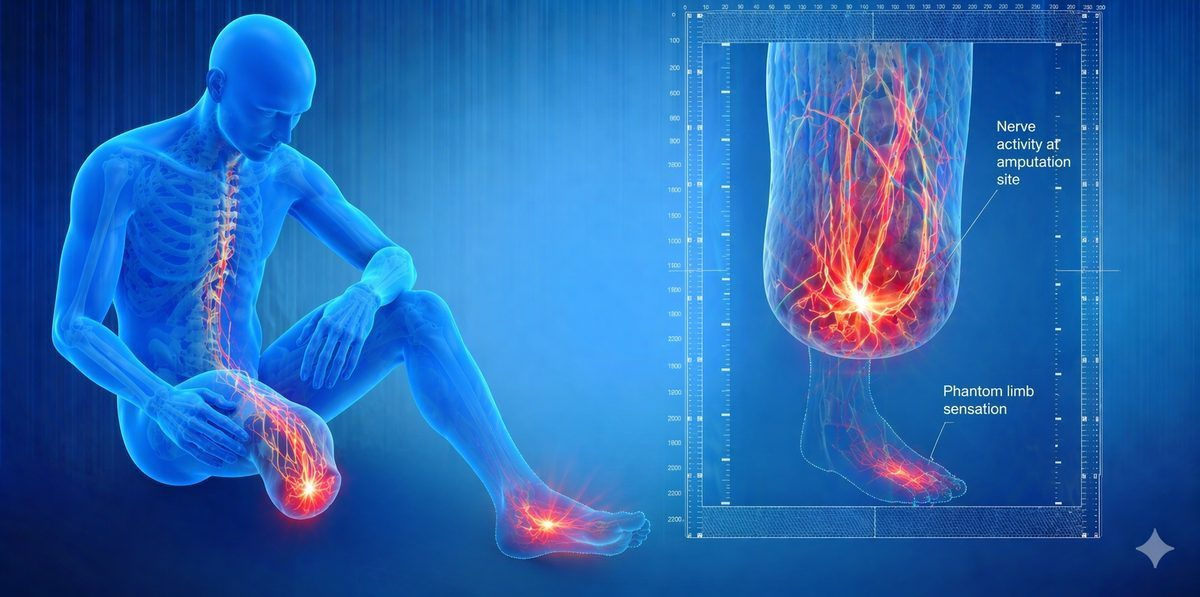

Illustration showing pain pathways in the brain and spinal cord related to phantom limb pain

The brain maps every part of the body in a region called the somatosensory cortex. After amputation, the nerves from the missing limb no longer send normal signals. The brain interprets this as pain. Over time, something called cortical reorganisation can make the problem worse. Nearby body parts begin to take over the brain area that used to represent the missing limb, and this remapping drives ongoing pain signals.

Diagram of the somatosensory cortex showing how phantom limb pain is generated in the brain

2. Peripheral Nerve Activity: The cut ends of nerves in the stump continue to fire abnormal electrical signals. These signals travel up to the brain and are interpreted as coming from the missing limb.

3. Cortical Reorganisation: The brain area that used to receive signals from the amputated limb starts to be taken over by neighbouring areas. This reorganisation is associated with increased phantom pain intensity.